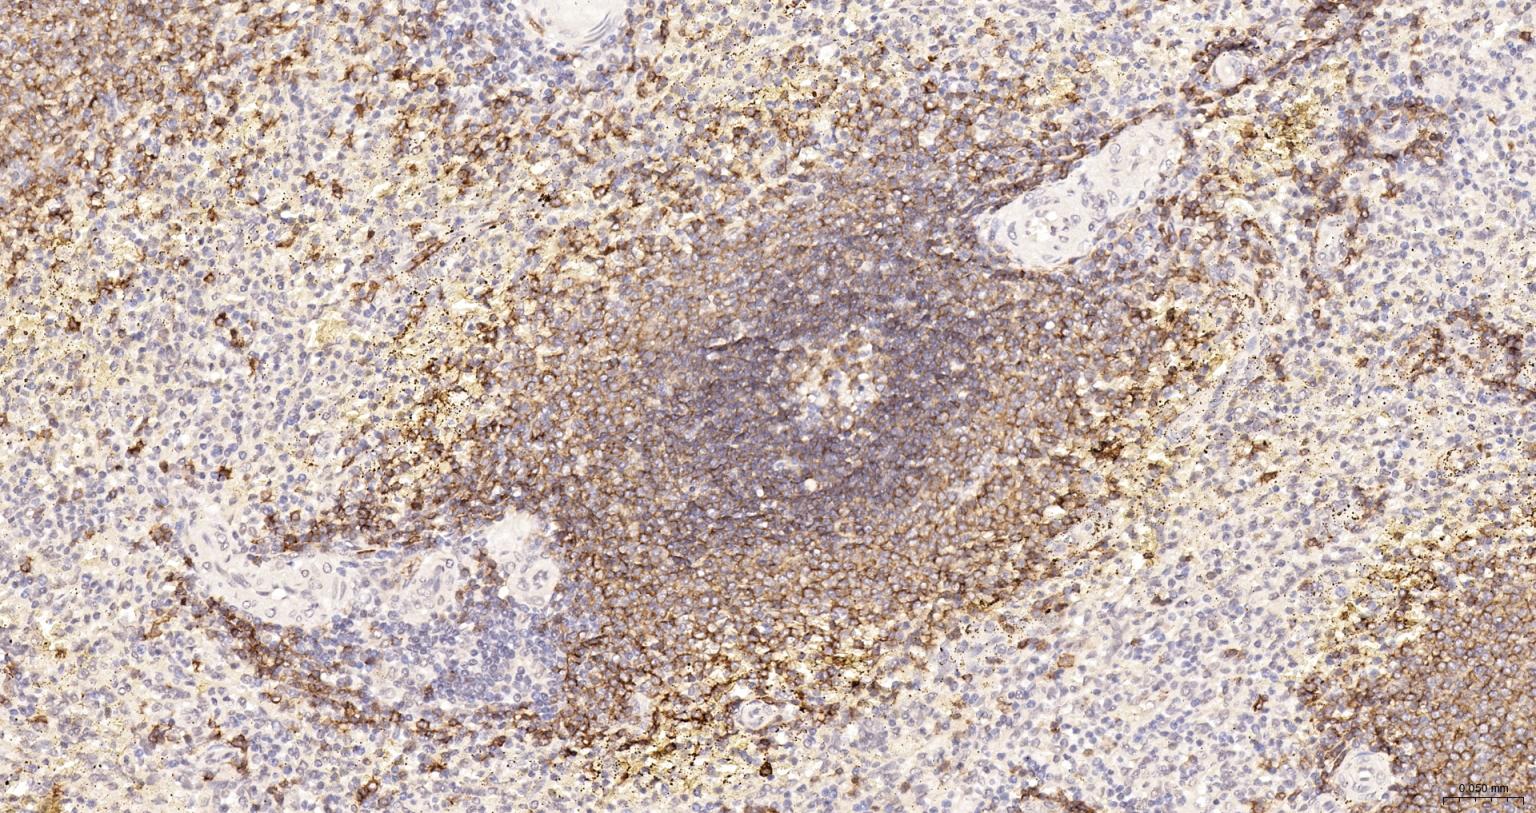

Paraformaldehyde-fixed, paraffin embedded Human Lymph; Antigen retrieval by boiling in sodium citrate buffer (pH6.0) for 15 min; The section was incubated with CD20 Recombinant Monoclonal Antibody (bsm-60638R-HRP) at 1:200 overnight at 4°C, and DAB (C-0010) staining.